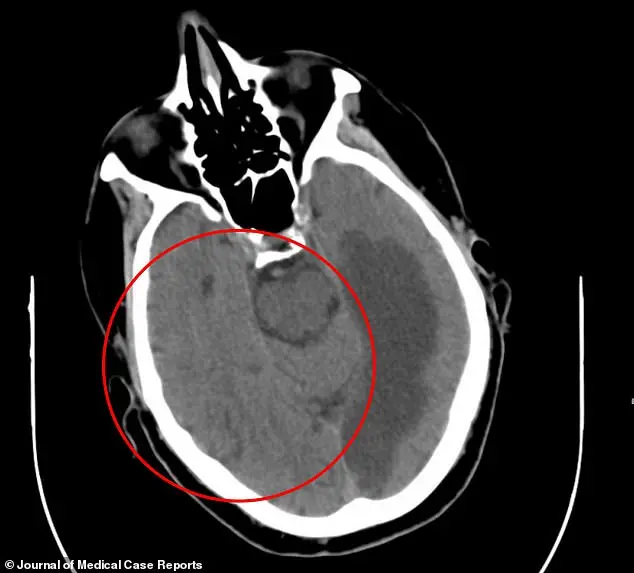

Medical imaging revealed the severity of the underlying issue.

A CT scan showed extensive brain damage, likely caused by a stroke that had affected the left temporal lobe and the occipital lobe.

The temporal lobe, responsible for language comprehension and memory, and the occipital lobe, which processes visual information, were both compromised.

The damage extended to the corpus callosum, the neural bridge connecting the brain’s two hemispheres.

This structure is critical for coordinating motor functions, sensory processing, and cognitive tasks.

The disruption of these areas, doctors theorized, was the root cause of the man’s uncontrollable movements.